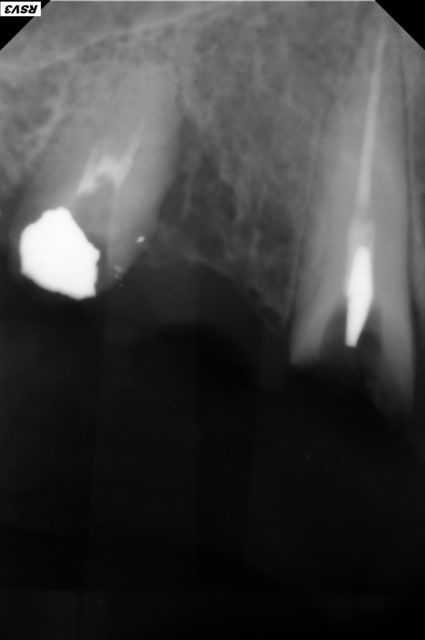

Bonjour à tous. Le bridge de cette patiente repose sur 13 et 15. IL est descellé avec une reprise de carie sur 13. J'ai programmé de le déposer. L'idéal serait de fraiser sur le pilier de 15. Pour des raisons économiques, je vais tenter de le déposer puis de le resceller. J'ai informé la patiente du risque de fracture de la 15 et d'éclats de céramique.

Tu as plein de carie sur la 12/13 et 15.

mon conseil sera: abstention ou gros boulot, car apparemment, il n'y a personne derrière cette 15 qui a déjà bien souffert...

Et une paro de surcharge sur la 5 + le reste autour qui est carié .

Dans les faits le bridges est venu sans aucune difficulté, par contre l'ancrage sur la 13 était un tenon fileté en or, une vraie saleté. Aucun résultat après 30 mn d'ultra son, ni avec la trousse de Gonon. J'ai fini par tirer dessus, dans l'axe de la racine avec une pince hémostatique, il s'est cassé et j'ai dû fraiser pour retirer le dernier fragment ...

La 15 n'est pas conservable.

Ci joint les radios.